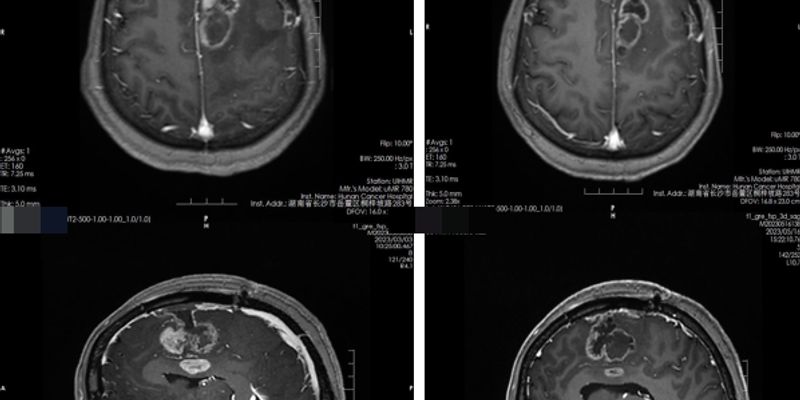

聚焦后颅窝脑膜瘤的分子分型与预后。最新研究揭示,携带高危CNAs的后颅窝脑膜瘤即使全切除,复发风险仍高。本文深度解读脑膜瘤的基因变异(NF2、CNAs、1p缺失、14q缺失)如何影响肿瘤位置和临床结局,为患者提供风险分层和辅助治疗选择的最新科学依据。 Read More... "后颅窝脑膜瘤最新研究:高危CNAs与不良预后、中线起源的关联解析"

《Nature Neuroscience》最新研究揭示了胶质瘤的侵袭性与大脑网络相互作用的深层机制。研究发现,高级别胶质瘤附近的神经元兴奋性增加,会加速肿瘤生长。这一发现为脑癌治疗提供了基于神经科学的全新药物靶点,有望开发出通过阻断神经元与癌细胞通讯来减缓肿瘤进展的新疗法。 Read More... "胶质瘤为何难以治疗?最新研究揭示神经活动如何驱动脑癌生长与侵袭性,指明未来新靶点"

血管母细胞瘤(HB)是一种中枢神经系统良性肿瘤。本文深度解析 VHL 和 TSC2 基因变异在 HB 诊断、遗传风险评估中的关键作用,并重点介绍 HIF-2α 抑制剂贝组替凡(Belzutifan)治疗 VHL 相关 HB 的临床疗效数据、作用机制及海外购买渠道,为患者提供最新的靶向治疗选择和用药指导。 Read More... "血管母细胞瘤 VHL/TSC2 变异解析:贝组替凡靶向治疗疗效、机制与海外购买渠道"